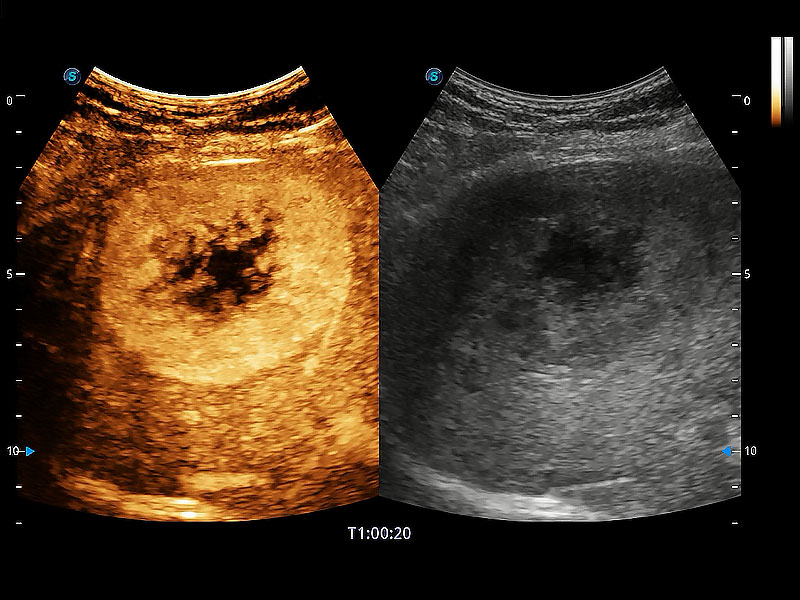

非线性融合造影成像充分利用谐波和基波信号,为难以观察的血流进行增强显像。可用于线阵、凸阵、微凸阵、相控阵探头。

极大提升超低速微细血流的检出能力,同时更精准地滤除软组织和超声信号,为兽用医生提供以往无法通过常规血流获得的疾病诊断信息。